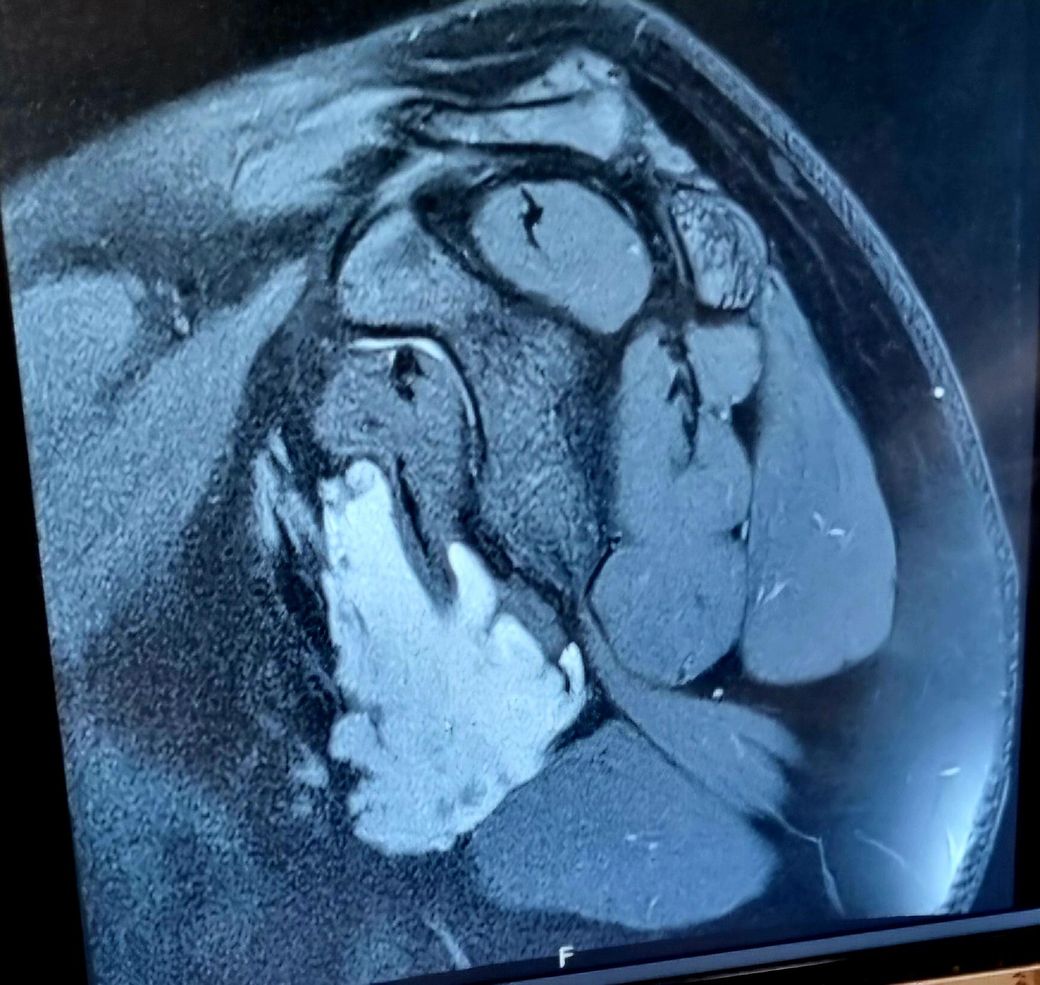

어깨 견관절 결절종인데 액와부에 생겻답니다

MRI 사진좀 확인해주세요 워치가 주사로 뽑을수있는 위치일까요?? 아니면 수술받아야하나요 MRA 촬영이 필요한걸까요??

액와부에 둥글고 밝게 보이는 부분이 결절종으로 추정되지만, 정확한 크기, 주변 조직과의 관계, 내부 상태 등을 파악하기 위해서는 MRI 영상의 다른 단면들을 추가적으로 확인해야 합니다. 결절종의 위치와 액체 점성도에 따라 주사 흡인을 시도해 볼 수 있으나, 액와부의 주요 구조물과의 근접성, 결절종의 크기, 내부 액체의 점성, 다발성 여부 등에 따라 어려울 수 있어요

판단 결과 주사 흡인이 어렵거나 재발이 잦고, 주변 조직 압박으로 인한 증상이 있다면 수술적 제거를 고려해야 합니다. 수술은 완전 제거가 가능하지만 흉터와 회복 기간이 필요하구요. 결절종이 혈관 주변에 있거나 수술을 고려한다면 MRA 촬영을 통해 혈관 구조를 자세히 확인하는 것이 도움이 될 수 있습니다.

따라서, 현재 MRI 사진만으로는 정확한 치료 방침을 결정하기 어려우며, 담당 의사와의 직접적인 상담과 진찰을 통해 결절종의 상태를 정확히 진단받고 적절한 치료 계획을 세우는 것이 가장 중요합니다